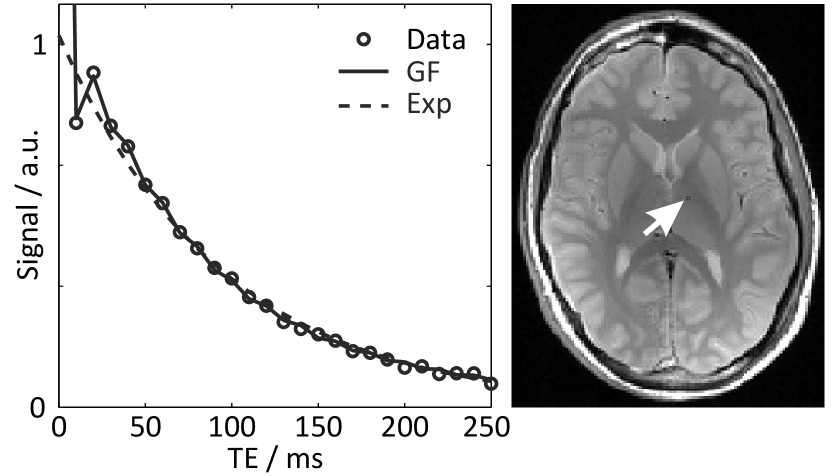

Refer to caption

Figure 1: Generating function (GF) and single exponential (Exp) fitted to the magnitude signal (circles) of a multi-echo spin-echo MRI acquisition of the human brain (25 echoes, single pixel = arrow). Because the GF is only valid at exact echo times, the solid curve is an interpolation for display purposes.

T2 mapping relies on a train of successively refocused spin echoes. In practical MRI, however, the assumption that these signals represent the true T2 relaxation decay is violated due to the formation of indirect echoes [16, 17]. The most notable consequence is a hypointense first spin echo which clearly disrupts the expected mono-exponential signal decay. A variety of attempts to better reproduce the echo amplitudes employ the EPG algorithm [18, 19, 20, 21] which considers different magnetization pathways in a recursive description. In 2007 Lukzen et al. [11] obtained an explicit analytical expression for the problem by exploiting the generating function (GF) formalism [22, 23]. In contrast to the EPG algorithm, the model formula can be implemented very efficiently using the fast Fourier transform. An example of the improved performance for an extended GF model [12] which includes non-ideal slice profiles is shown in Fig. 1 for human brain MRI data.